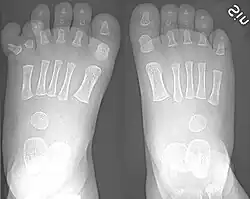

There are normally five toes present on each human foot. Each toe consists of three phalanx bones, the proximal, middle, and distal, with the exception of the big toe (Latin: hallux). For a minority of people, the little toe also is missing a middle bone. The hallux only contains two phalanx bones, the proximal and distal. The joints between each phalanx are the interphalangeal joints. The proximal phalanx bone of each toe articulates with the metatarsal bone of the foot at the metatarsophalangeal joint. Each toe is surrounded by skin, and present on all five toes is a toenail.